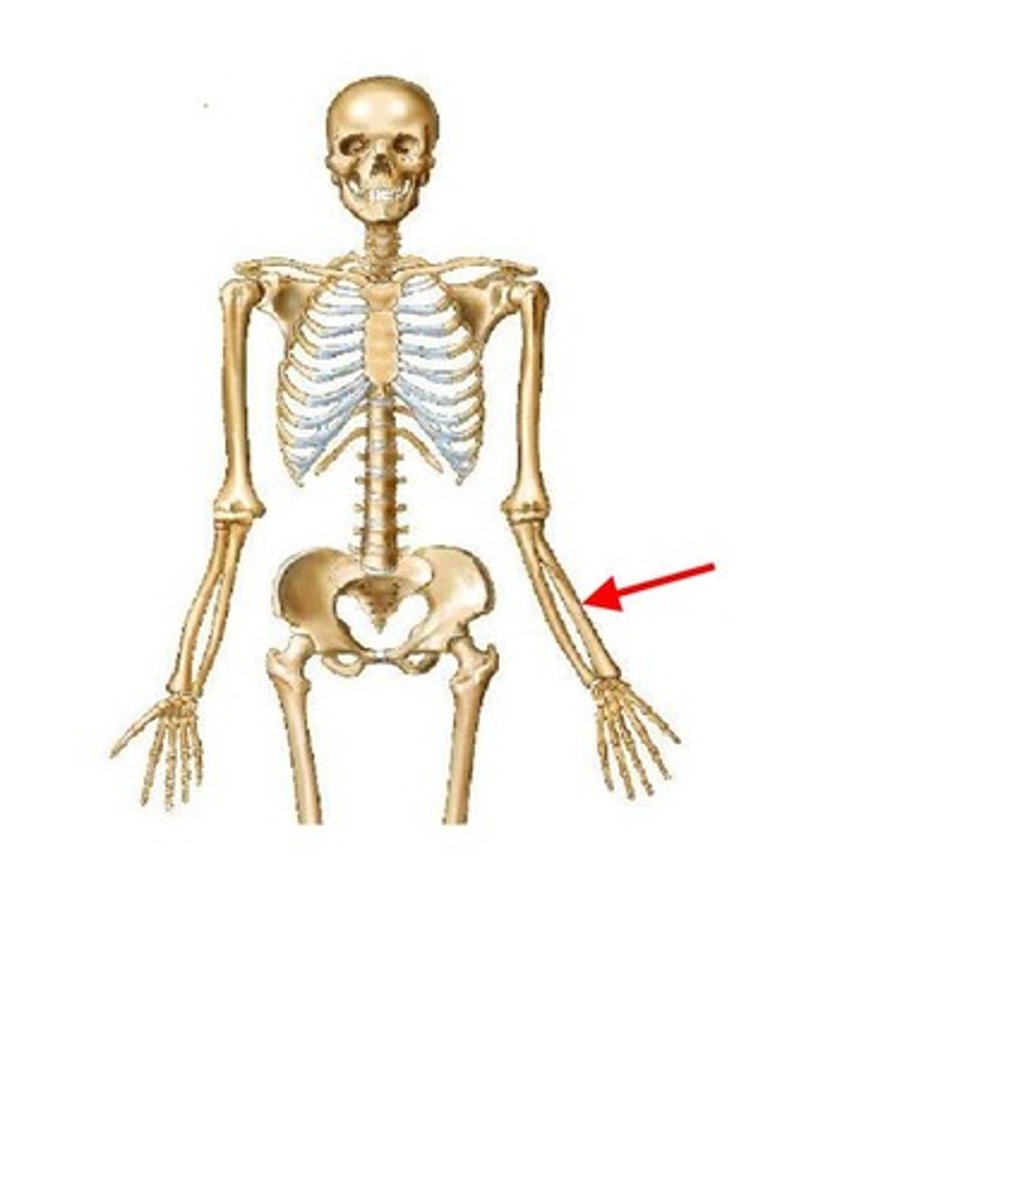

ulna

ID bone

radius

ID bone

humerus

ID bone

ulna

ID bone

radius

ID bone

ulna

ID bone

radius

ID bone

humerus

ID bone